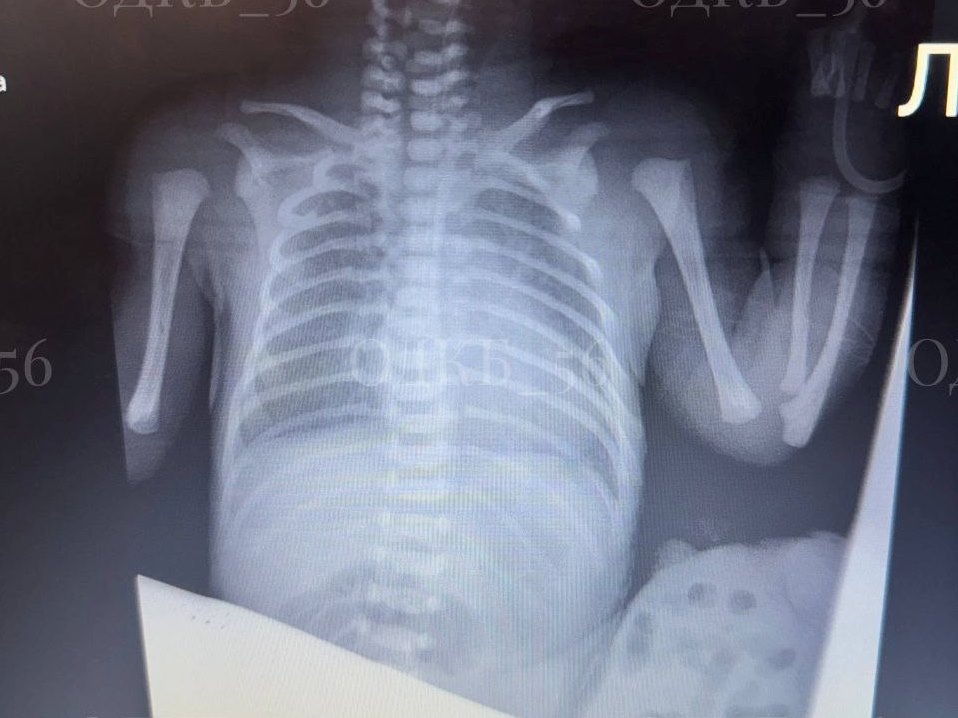

В Оренбурге хирурги спасли жизнь новорожденному с органами вне тела

Малыш родился с серьезной и довольно редкой патологией. Некоторые его внутренние органы оказались в пуповине за пределами тела ребенка. В областную детскую клиническую больницу поступил новорожденный пациент с омфалоцеле. Грыжа пупочного канатика имела довольно большой размер. Хирурги приняли решение оперировать. Омфалоцеле – это довольно редкая врожденная патология, при которой внутренние органы, чаще всего печень и кишечник, выходят за пределы брюшной полости и попадают в пуповину, формируя «мешочек». Такая патология встречается от 1 до 5 случаев на 10 000 новорожденных. Сразу после подготовки младенцу провели операцию. Бригада детских хирургов устранила дефект, вернула внутренние органы в брюшную полость и выполнила пластику, сформировав из собственных тканей ребенка пупок. Операция прошла благополучно. В послеоперационном периоде ребенок находился и получал лечение в отделении реанимации, под постоянным контролем хирургов и реаниматологов ОДКБ. В настоящее время, ввиду хорошего сам

Фото: ОДКБ